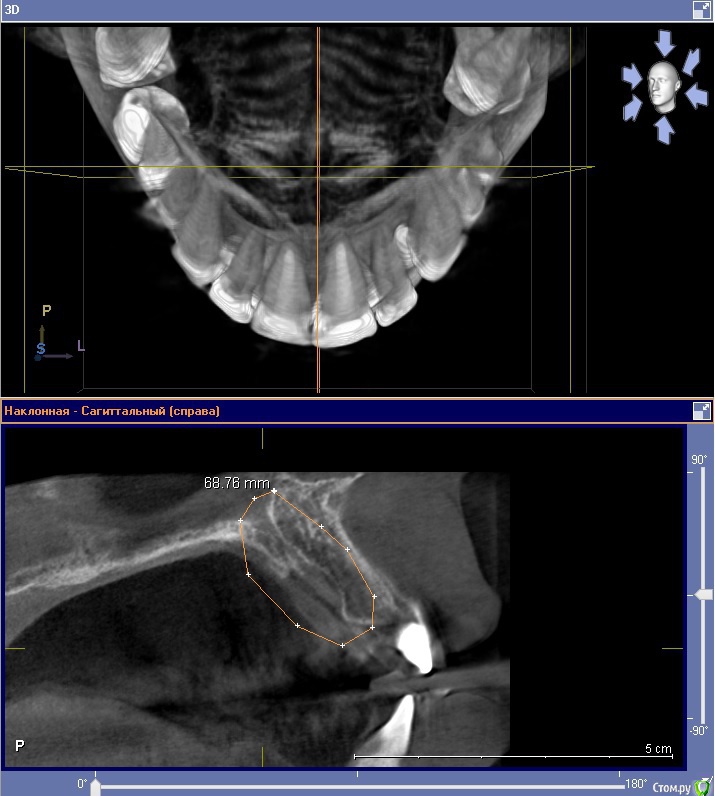

sergei995 Опубликовано 27 марта, 2016 Поделиться Опубликовано 27 марта, 2016 (изменено) Здравствуйте! Проконсультируйте, пожалуйста. В 2006м году у меня на небе ровно по центру образовалась небольшая припухлость, которая пару дней болела. Я сходил к врачу, сделал рентген - все было в норме. Посоветовали пополоскать и всё. Так я и сделал, болезненность прошла, но легкая выпуклость в этом месте осталась, которая совершенно не беспокоила. Пару раз только за 10 лет, когда простывал, это место становилось чуть болезненным (на день). Недавно сделал КТ (по другому вопросу - планирую имплантацию 6ки). И вот такая картинка получилась. Мне сказали, что это место - место "резцового отверстия". И действительно, у меня там там присутствует некоторое образование. Нужно ли что-то с этим делать? Нужно ли иссекать и дренировать эту "полость" (видимо, это полость)? (Мой врач предлагает пока просто наблюдать) При этом слизистая нёба не изменена, отечность отсутствует. Насморками и гайморитами не страдаю вообще. Прикладываю результаты КТ - два наиболее характерных среза. Заранее благодарю за помощь! Изменено 27 марта, 2016 пользователем sergei995 Ссылка на комментарий

___49___ Опубликовано 28 марта, 2016 Поделиться Опубликовано 28 марта, 2016 Очень похожа на кисту резцового канала, образование не злокачественное, а доброкачественное, растет медленно рассасывая окружающую кость , при определенных условиях может нагноится. Лучше убрать хирургически в плановом порядке с последующим не продолжительным ношением защитной небной пластинки. 1 Ссылка на комментарий

Doctor Vlad Опубликовано 29 марта, 2016 Поделиться Опубликовано 29 марта, 2016 Размер не большой, возможно киста резцового канала! я б понаблюдал. периодически контроль роста. при обострении провести диагностическую пункцию на наличие кистозной жидкости Ссылка на комментарий